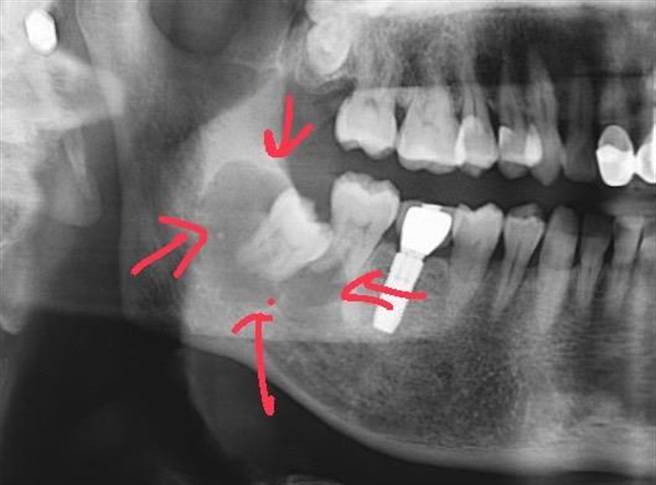

许多民眾因为长智齿而苦恼,图为一名患者到牙科就医后,从X光影像发现右下智齿周边有异常病灶,高医医师蔡承熹发现有3、4公分大小的囊肿,已将未长出的智齿包覆住。为避免进一步造成颚骨破坏,医师安排全身麻醉刮除囊肿部位,并将智齿及邻近已被波及的第二大臼齿一併拔掉。(高医冈山医院提供/林瑞益高雄传真)

另名66岁张先生M则是到诊所例行性洗牙时,从X光影像发现右下智齿周边有异常病灶,转往医院口腔颚面外科诊查,发现是3、4公分大小的囊肿,已将未长出的智齿包覆住,为避免进一步造成颚骨破坏,医师安排全身麻醉刮除囊肿部位,并将智齿及邻近已被波及的第二大臼齿一併拔掉。